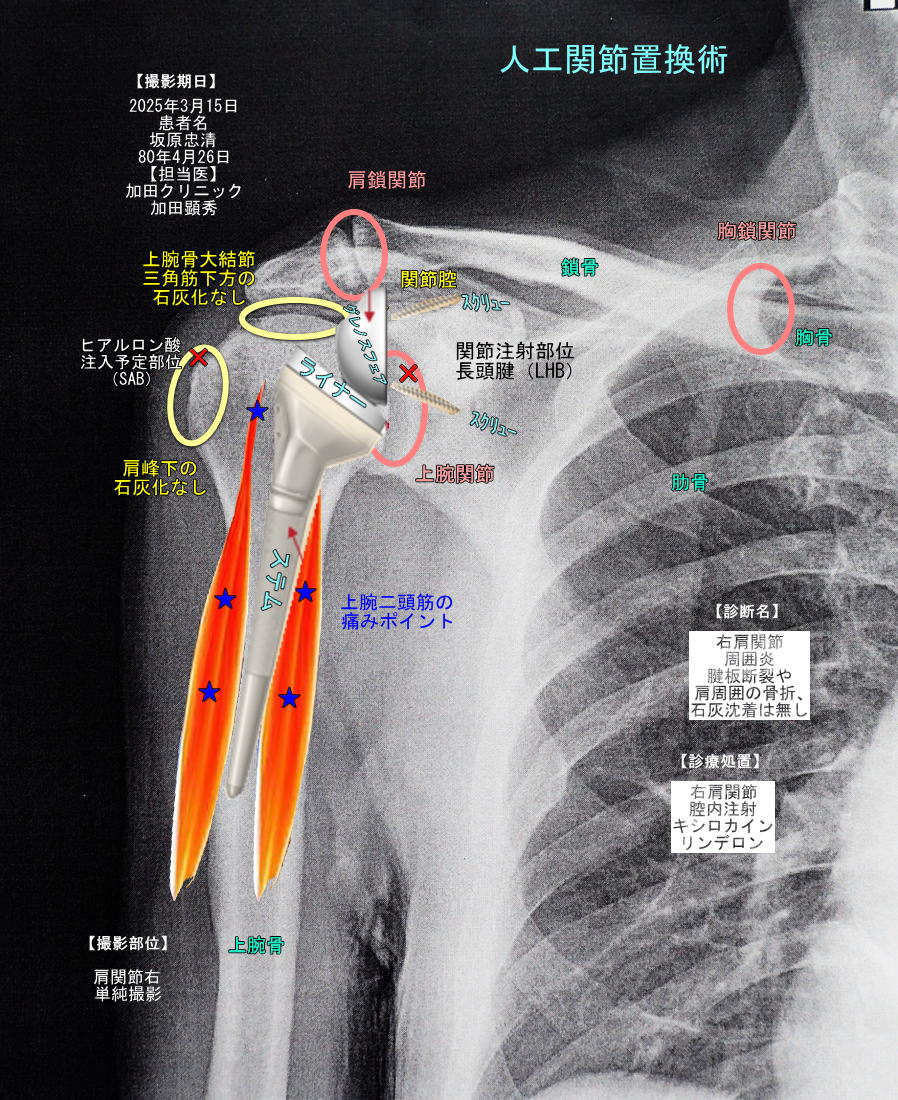

| ヤバイ!右折が出来ないぜ! 3月15日(土)曇 右にハンドルを回し戻そうと右手を上げようとしたが上らず」! 50肩で右腕の痛みが酷く30度ほどしか上げられず、右折ハンドルがきれない。 色々調べたがステロイドとキシロカインの痛み止め処置が出来るクリニックが見つからず、 加田クリニックを探し出し明日朝一で診て貰うことにした。 院長:加田顕秀(昭和61年1986年金沢医大卒・39年前なので66歳?) 日本整形外科学会認定リウマチ医 日本整形外科学会認定スポーツ医 石灰沈着性腱板炎:肩についている筋肉や腱などの組織に石灰が溜まり、 その溜まった石灰が溶け出して関節の中に入り込むと、炎症を起こし痛みになる。これが五十肩石灰化の症状である。 上腕二頭筋の長頭腱(LHB)の炎症と、腱板損傷およびそれに伴う滑液包炎 LHBにステロイド注射と、 肩峰下滑液包内(SAB)にヒアルロン酸注入をセットで行う。この二つでおおかたカバーできる。 まあ、現在これ以外にはオペしかないのでやってみるしかない! 単純デジタル撮影の結果、腱板断裂や肩周囲の骨折、石灰沈着は無し。 骨折等も無く肩関節周囲炎(50肩)と病名決定。 単純デジタル撮影した右肩X線コピーに、撮影期日、撮影部位、診断名、診療処置、関節名、注射部位など入れて画像作成。 SAB:肩峰下滑液包内(SAB) そのため、炎症を起こしやすく滑液が増えたり滑液を包んでいる滑液包が肥厚して痛みが現れる。 |